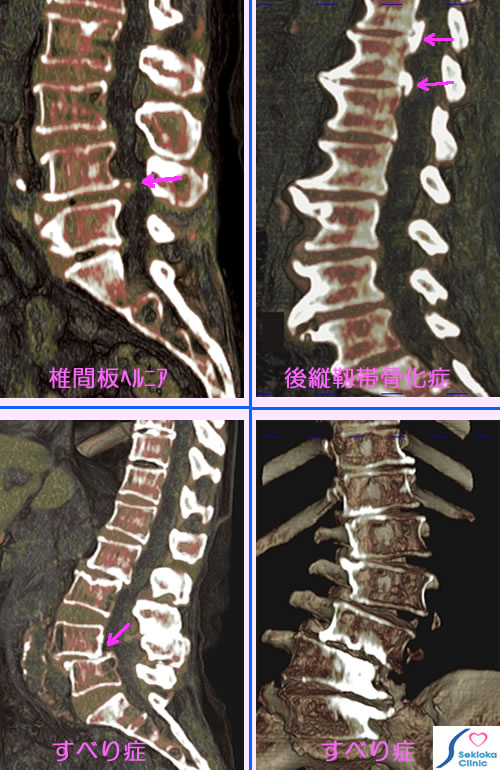

腰椎の病気: 腰痛、下肢痛

自覚症状

腰痛、下肢の痛み、下肢のしびれ、歩行障害など

診断

神経の検査、X線撮影、CT。精査には腰椎の任意断面が観察できるMDCT、MRIが有用です。

治療

痛みが軽い時は鎮痛剤、湿布薬。痛みが強い時はトリガーポイントの神経ブロック麻酔を行っています。強い痛みや歩行障害が残存する時は手術。手術の適応がある時は 整形外科に紹介しています。